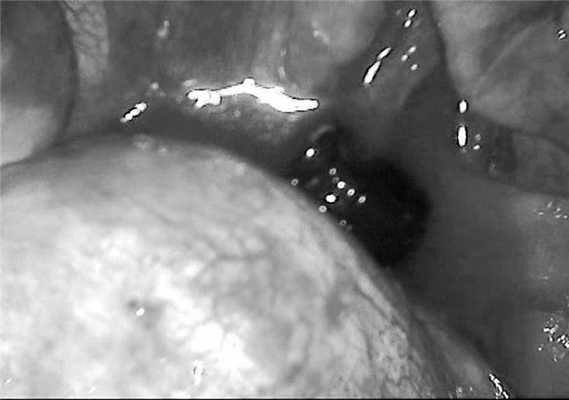

У 13 раненых огнестрельные повреждения груди были проникающими (рис. 4, в). При отсутствии показаний к торакотомии вмешательство ограничивали первичной хирургической обработкой и дренированием плевральной полости (7 наблюдений). Несмотря на проникающие ранения, при рентгенологическом исследовании инородных тел (пуль) в этих наблюдениях выявлено не было. Двум больным этой группы в отсроченном порядке была выполнена торакоскопия в связи с выявленным инородным телом легкого или плевральной полости на рентгенограмме груди в послеоперационном периоде. В одном из этих наблюдений выполнены пневмотомия и удаление резиновой пули калибра 18 мм, ушивание раны легкого П-образными швами, санация и дренирование плевральной полости. В другом наблюдении резиновая пуля калибра 18 мм лежала в заднем костно-диафрагмальном синусе слева (рис. 5), Рисунок 5. Фотография при торакоскопии: в заднем синусе левой плевральной полости видна резиновая пуля калибра 18 мм. произведены ее удаление, санация и дренирование плевральной полости.